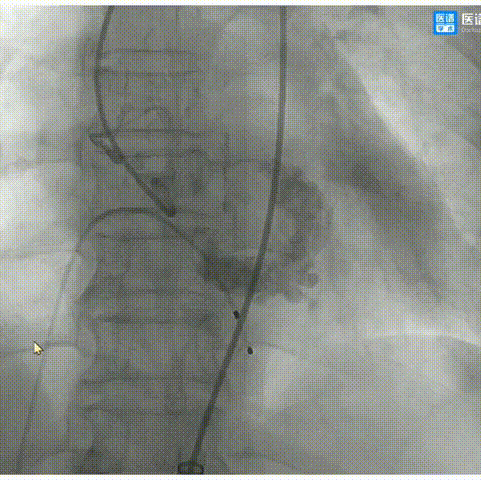

8.撤出猪尾导管,造影显示无瓣周漏,手术圆满成功。

最终,在整个团队通力合作,首次使用TaurusElite瓣膜,就可独立开展,并且术中过弓顺利、定位精准,一次性释放成功,术后无瓣周漏,跨瓣压差稳定在3mmHg,完美的完成了一次TAVR手术。